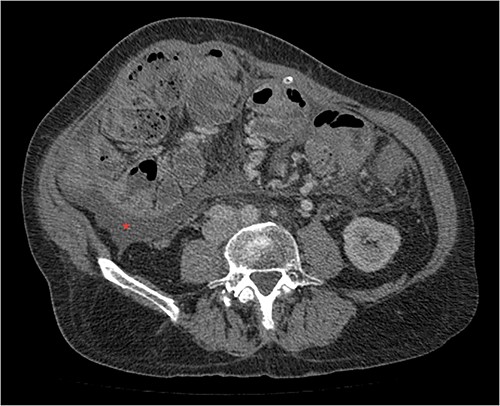

His clinical history and contrast-enhanced computed tomography (CT) findings (Figs 1–3) were compatible with EPS in Stage 4 (Table 2). Laboratory tests were non-specific, showing inflammation and malnutrition. He underwent nutritional support, corticosteroids and surgery. In surgery, fibrocollagenous membrane resection and enterolysis were done. Postoperative period was complicated by pneumonia treated with piperacillin+tazobactam and later bacterial peritonitis treated with ertapenem. The patient was discharged after 29 days with adequate nutrition and asymptomatic.

Portal phase coronal section image on CT showing loops wrapped in a membrane-like structure (arrow).

Imaging exams, mainly CT are important to evaluate causes of bowel obstruction [4]. Dilated or non-dilated small intestine loops may be wrapped in a membrane-like structure, proximal bowel dilatation, thickened peritoneum with diffuse or local calcification, and loculated ascites are some of the findings on CT [1, 12]. Barium X-ray provides a clue to bowel encapsulation, showing clustered loops of the small intestine in the center of the abdomen, known as the cauliflower sign [4]. Ultrasound and magnetic resonance imaging may give a clue but are rarely used [1, 12].